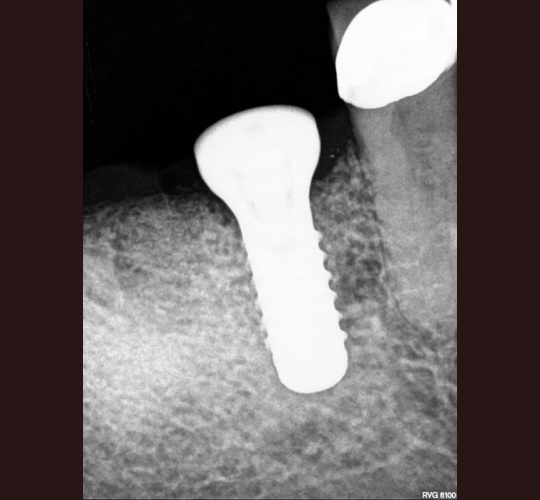

Implants: Case #8

Patient presented with a sinus tract, the radiograph showed apical resorption on distal root. The tooth was extracted and the mesial root socket was grafted allowed to heal for 4 months and a Straumann tissue level implant was placed. 8 weeks later the crown was placed.